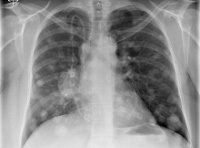

Диагноз выставляется с учетом анамнеза, клинических проявлений, результатов инструментальных и лабораторных исследований. Пациентов с подозрением на метастазы в легких направляют на рентгенографию грудной клетки, позволяющую оценивать состояние легочной ткани, определять тип, характер и количество вторичных новообразований, наличие выпота в плевральной полости. Пациентам также назначают КТ легких – эта современная методика дает возможность выявлять мелкие метастазы диаметром менее 0,5 мм, в том числе расположенные субплеврально.

При необходимости снизить лучевую нагрузку (при метастазах в легких у детей, при многочисленных исследованиях для выявления первичного очага и метастатических поражений других органов, при продолжительном наблюдении) и подозрении на наличие мелких метастазов проводят МРТ легких – эта методика позволяет обнаруживать вторичные очаги диаметром менее 0,3 Метастазы в легкие подтверждают на основании результатов цитологического исследования мокроты и плеврального выпота или гистологического исследования биоптата, полученного в процессе бронхоскопии, чрескожной пункционной биопсии легкого или (реже) открытой биопсии.

Для выявления метастазов других локализаций проводят расширенное обследование, включающее в себя УЗИ органов брюшной полости, сцинтиграфию костей скелета, КТ и МРТ позвоночника, КТ и МРТ головного мозга, УЗИ органов малого таза, УЗИ забрюшинного пространства и другие исследования. Метастазы в легкие дифференцируют с периферическим раком легких, доброкачественным новообразованием легкого, пневмонией, кистой легкого и туберкулемой.